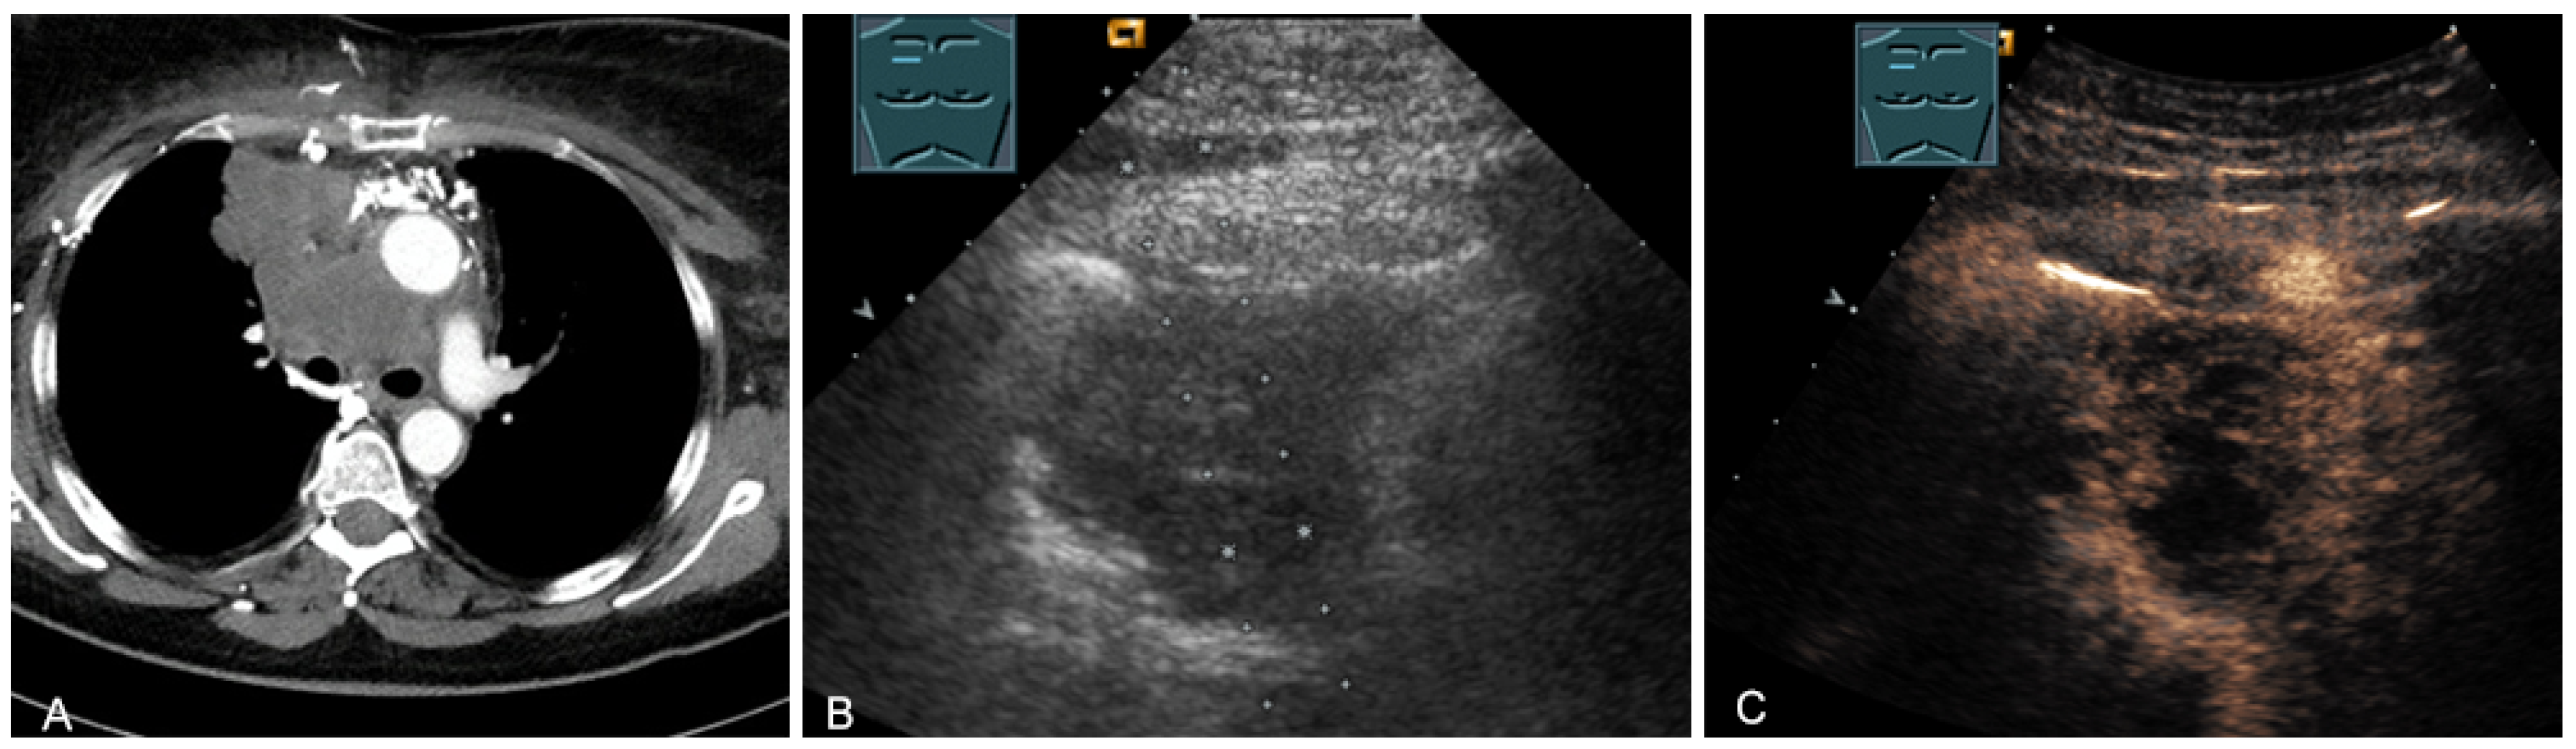

Figure 17.

A young patient with tumor formation in the paravertebral mediastinum on CT (provided by Prof. Dr. Andreas H. Mahnken, Marburg, Germany) (A), B-mode US (B), and CEUS (C), surgically confirmed as schwannoma.